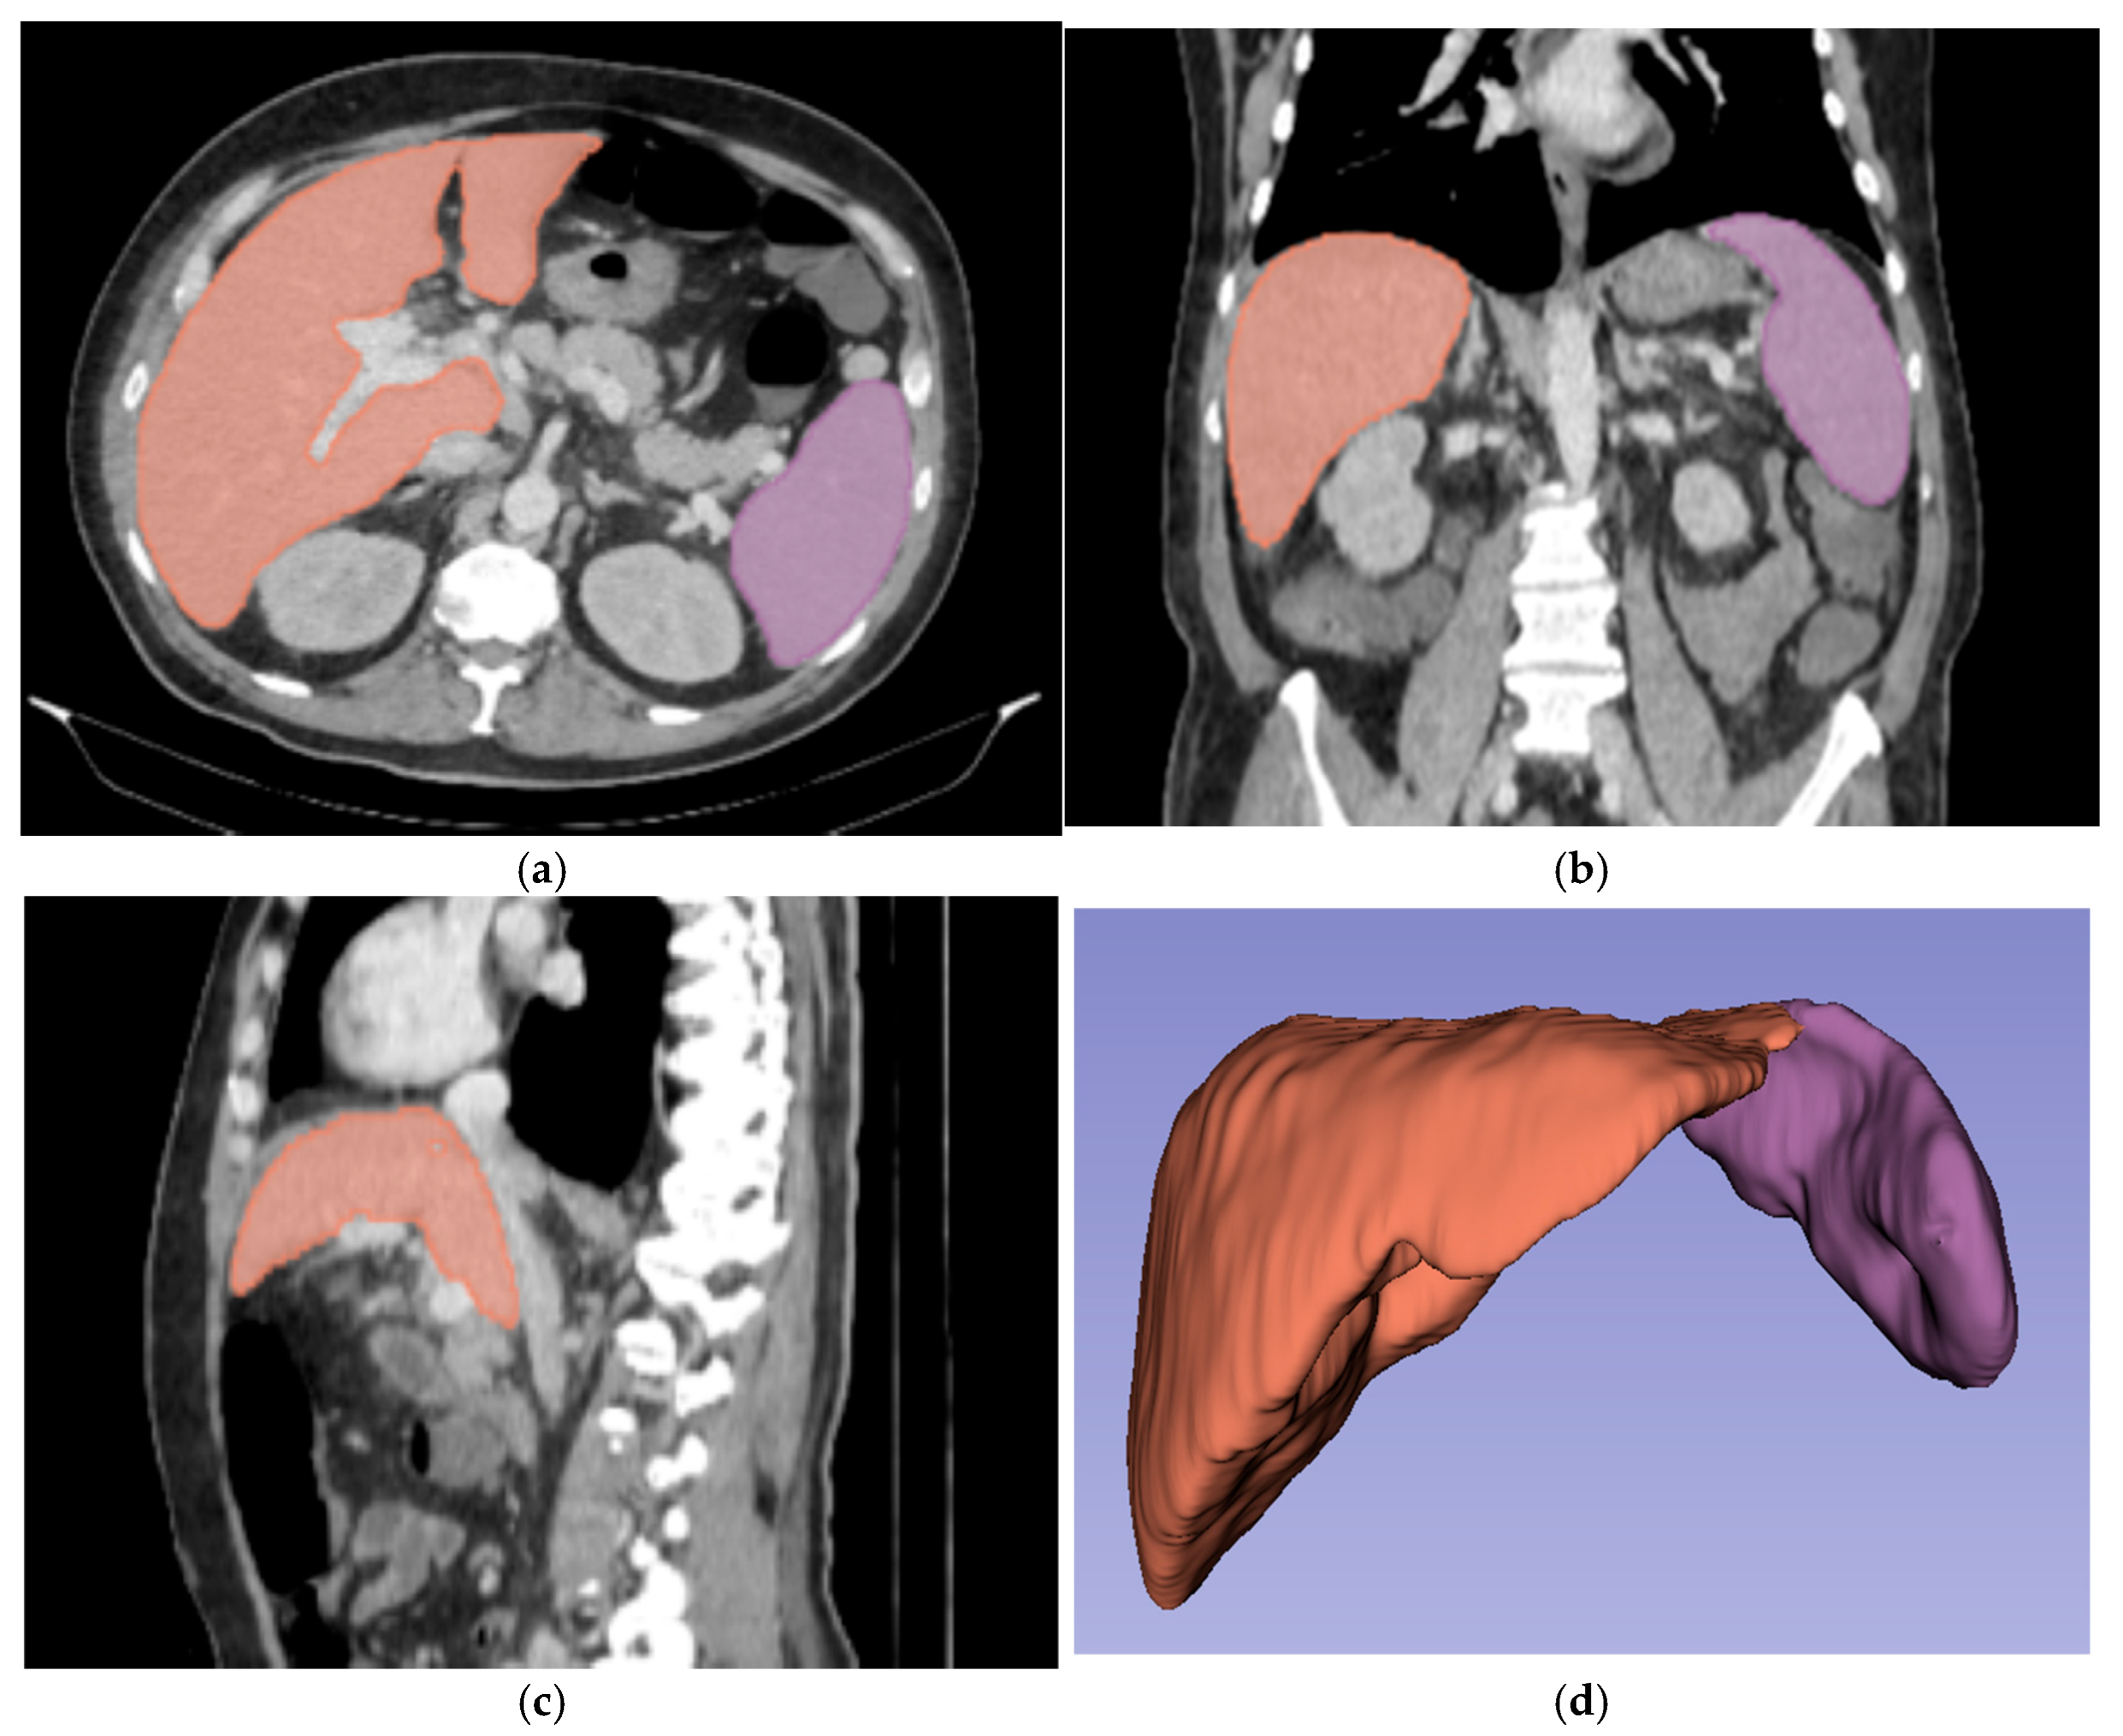

2.4.1. Image Segmentation and Radiomic Feature Extraction